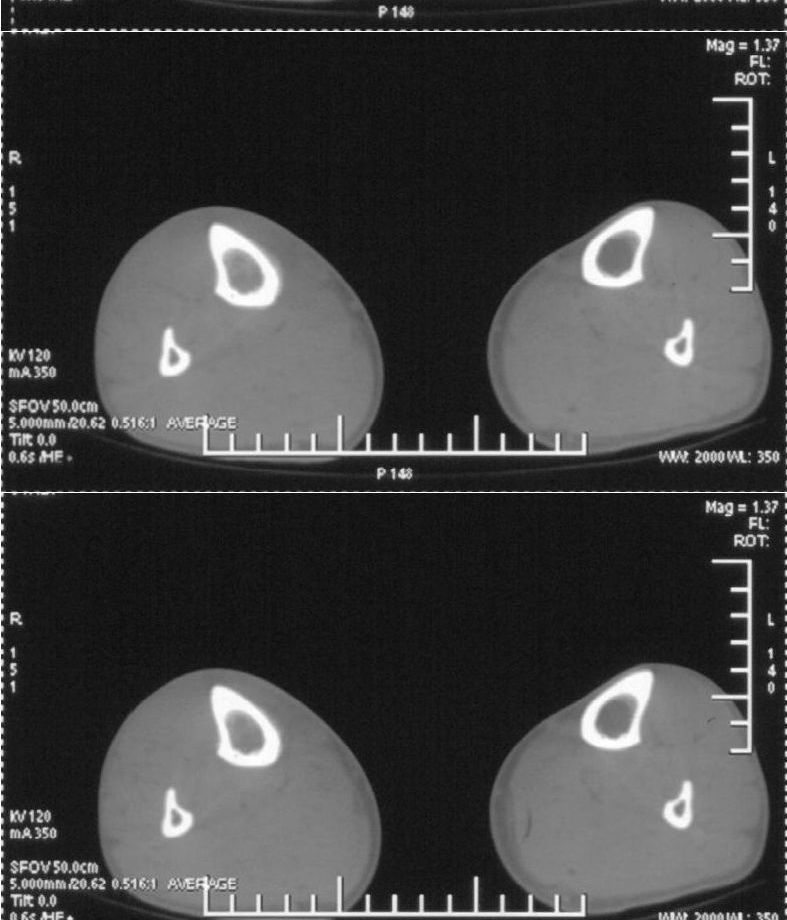

男,42岁。4个月前钢筋钝伤右侧小腿部,当时因无明显外伤,未引起重视。一周后因受伤腿部疼痛,发现肿胀,随后到当地医院进行检查(2008年4月16日)。因未发现骨质异常未引起重视,仅仅进行口服抗生素治疗处理。经过一段时间治疗但未见明显治疗效果在5月29日又进行x线检查,发现有胫骨密度上段密度增高,又进行抗炎治疗,仍未见效果。又在7月3日进行x线检查,仍然报告有胫骨上端密度增高,并建议ct检查。以下是相关检查结果:

该患者到某三级医院进行会诊,并重新作了平片检查,认为畸形性行骨炎:

髓腔密度呈絮状增高,胫骨上端内侧可见层状骨膜反应,考虑骨髓炎.

髓腔密度呈絮状增高,胫骨上端内侧可见层状骨膜反应,肌间隙模糊,考虑骨髓炎.